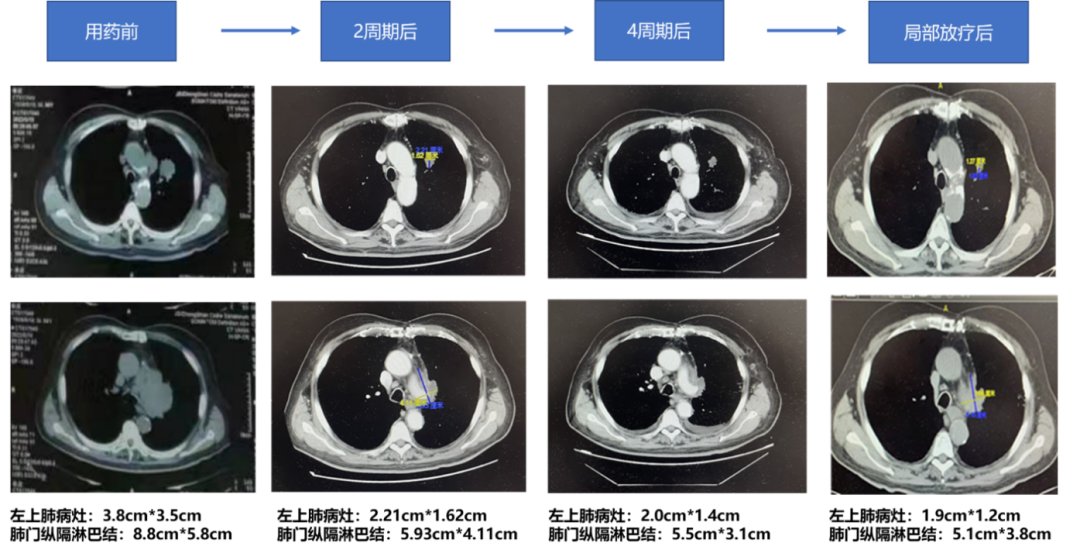

2022-08-12(2周期后)胸部CT:左肺上叶分叶状结节,较前稍缩小,现约1.62cm*2.21cm。左肺门、纵隔见多发大小不等淋巴结,部分有融合,形成不规则软组织肿块,包绕临近血管,较大截面约5.93*4.11cm;两肺肺气肿、肺大泡;两肺散在少许索条,胸膜下为主,呈间质性改变。两肺多发小结节影,较大一枚约0.78cm;双侧锁骨上小淋巴结。两侧未见明显胸腔积液。

2022-09-27(4周期后)胸部CT:左肺上叶分叶状结节,较前稍缩小,现约1.42*2.0cm;左肺门稍肿大淋巴结,较前稍饱满,现约2.71*1.92cm。纵隔多发大小不等淋巴结,部分有融合,形成不规则软组织肿块,包绕临近血管,较大一处现约5.54*3.12cm,前约5.93*4.11cm,较前稍缩小。双侧锁骨上小淋巴结,变化不大。两肺肺气肿、肺大泡,两肺散在斑片索条影,胸膜下为主,呈间质性改变,较前明显;两肺散在小结节影,较大一枚仍0.78cm,变化不大。两侧胸腔少量积液,较前稍增多。

2022-11-10(放疗后)胸部CT:左肺上叶分叶状结节,较前稍缩小,现约1.89*1.27cm,原约1.42*2.0cm;左肺门稍肿大淋巴结,较前相仿,现仍约2.71*1.92cm。纵隔多发大小不等淋巴结,部分有融合,形成不规则软组织肿块,包绕临近血管,较大一处现约5.1*3.86cm,原约5.54*3.12cm,较前稍缩小。双侧锁骨上小淋巴结,变化不大。两肺肺气肿、肺大泡;两肺散在斑片索条影,胸膜下为主,呈间质性改变,较前稍改善。右肺中叶新增实性结节,约0.98*0.9cm;两肺散在小结节影,较大一枚仍约0.78cm,变化不大。两侧胸腔少量积液,较前减少。

疗效评估:PR